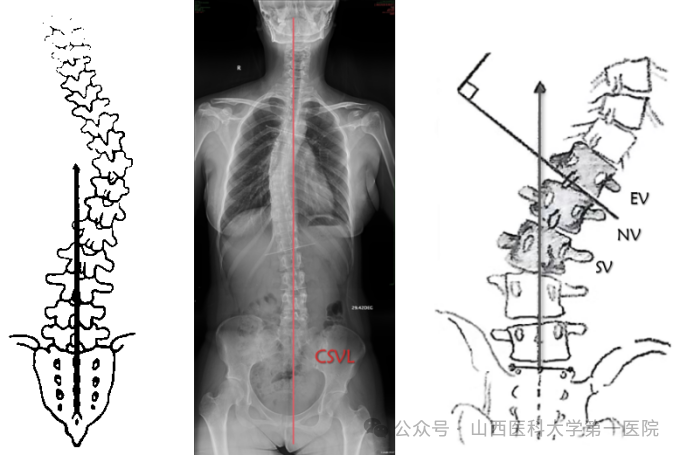

3. 骶骨中心垂直线(CSVL)

从S1上缘中点垂直于地面绘制的垂线,它描绘了脊柱相对于骨盆的冠状位置。

4. C7垂线(C7PL)

C7垂线是C7椎体中心垂直向下的直线,与X线片垂直边缘平行。通过测量C7垂直线与S1(CSVL)中心垂线之间的横向距离,可以确定冠状面的平衡。C7PL-CSVL代表C7PL和CSVL的水平间距。C7PL位于CSVL右侧为正值,左侧为负值,C7PL-CSVL>2cm定义为冠状面失衡。

5. TP点(transitional point)

TP点定义为胸弯下端椎体(LEV)与腰弯上端椎体(UEV)之间的中点。TP点与骶骨中线横向位置关系,可以确定侧凸是平衡还是失衡(R/L)。